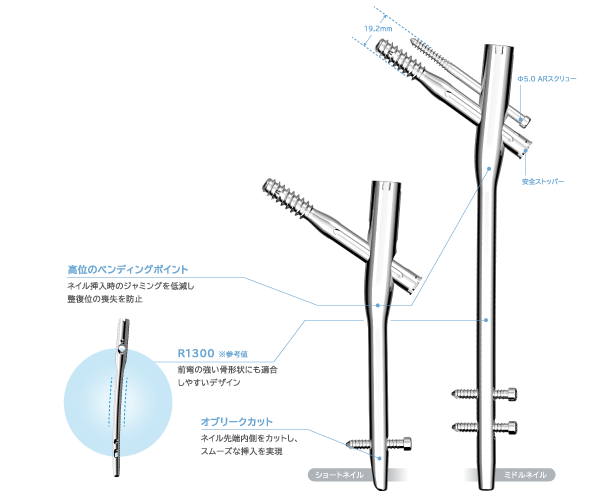

Dedicated to Japanese

Nail design pursuing compatibility with the femoral marrow cavity of Japan

- Short Nail

- Middle Nail